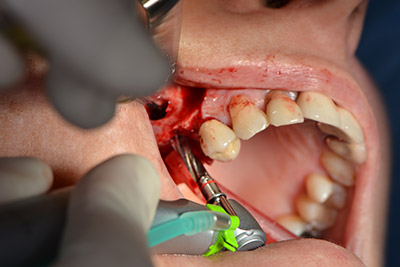

The next step was the sinus floor elevation with simultaneous implantation. The Implantmed also had a presetting at the first position for the buccal fenestration of the maxillary sinus wall.

The fenestration was prepared at 35,000 rpm and then the nasal mucosa were prepared in the cranial direction (Fig. 13 to 14).